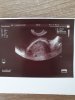

A to z tydzień temu

No I wszystko idealnie. Masz clr 3.3 milimetry. Nie mam pojecia dlaczego obliczyli ci 5+3 bo wedlug mnie powinno byc 6 biorac pod usage ze usg dodaje 14 dni. Jestem pewna ze dzis lub jutro zobaczylabys serduszko. Wedlug mnie wszystko wyglada idealnie ale jesli sie tak bardzo martwisz to moze idz jutro na usg. Moze do innego lekarza. Lepiej isc I sie uspokojisz niz sie stresowac

Ja się poprostu boję, że ta ciąża zatrzymała się na 5+3 i ta myśl wykańcza mnie psychicznie😔

Napewno sie nie zatrzymala bo ewidentnie rosnie w jak najlepszym tepie. Jezeli zarodek mialby 6 milimetrow a nie bylo by serduszka to bym sie martwila. Tym bardziej ze doskonale wiesz kiedy doszlo do zaplodnienia